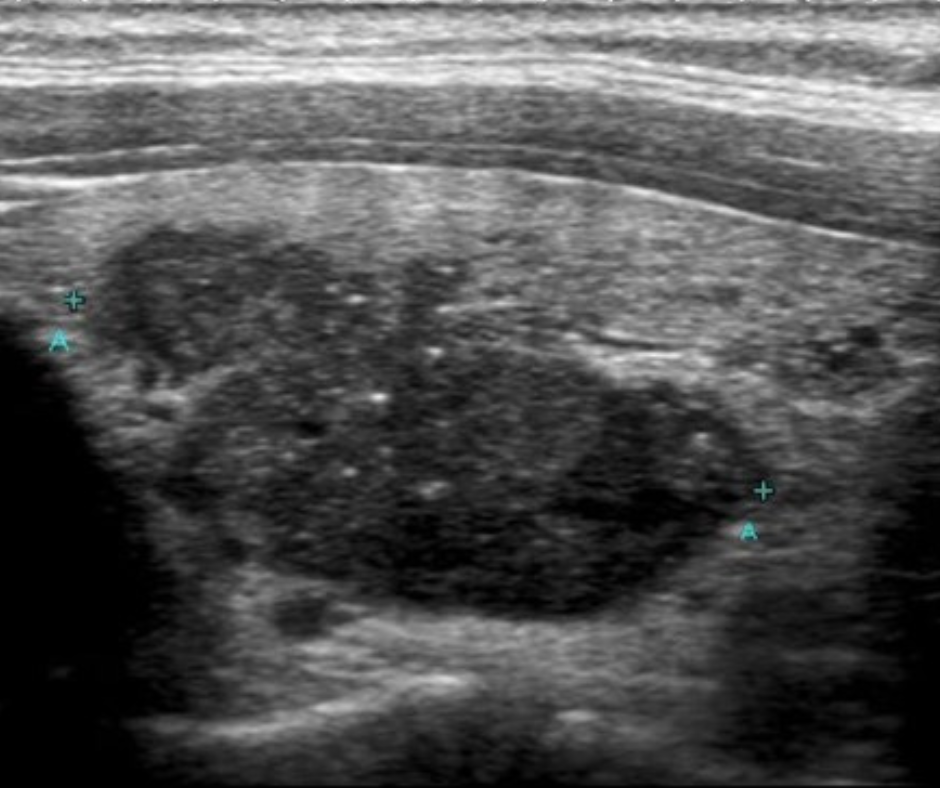

Figure 1: Ultrasound image of a cancerous thyroid nodule